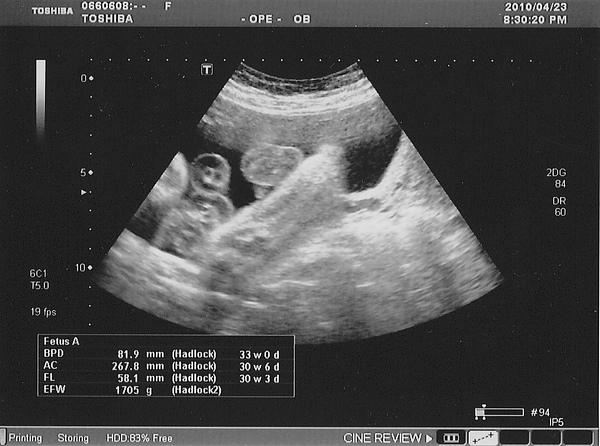

昨天是滿三十周的日子

肚子裡的小小倉

是各大頭寶寶

因為他的週數已經邁向三十三週

重量一千七百多公克

比一各月前重了六百多公克

但是目前的小小倉頭部仍在我的右手邊

屬於胎位不正的位置

PS.不要問我這是哪各位置 因為我也不知道